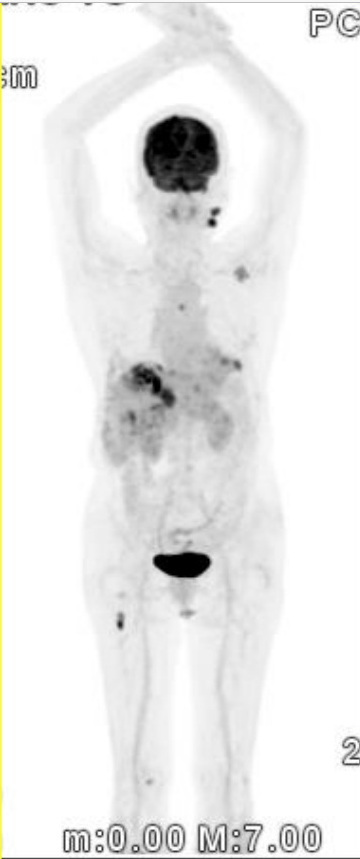

After the minimally invasive center team and the international department of all-out treatment, the disease has been quickly controlled, recently a PET CT shows the result was far exceeded expectations!

PET CT re-evaluation om 20th May 2023.